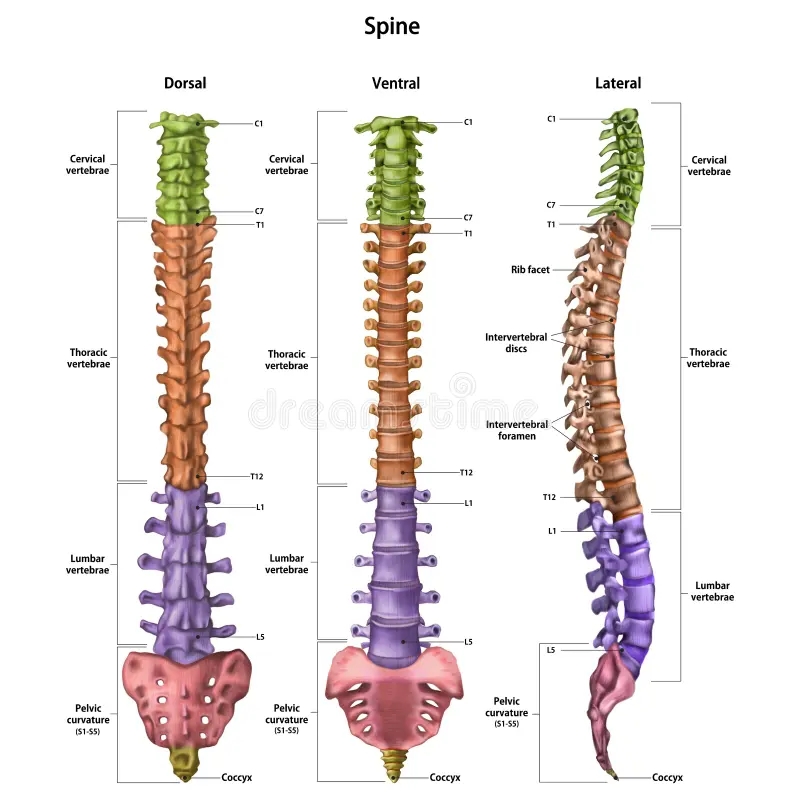

The Vertebral Column Anatomical Chart is a detailed illustration that breaks down the spine into its individual components. From the cervical spine in the neck to the coccyx at the base, each vertebra plays a unique role in supporting the body and allowing for movement.

By studying the Vertebral Column Anatomical Chart, healthcare professionals, students, and individuals can learn about the different regions of the spine, including the curvature of the vertebrae, the function of intervertebral discs, and the role of spinal nerves in transmitting signals throughout the body.

Whether you’re a medical professional looking to enhance your knowledge or someone curious about the inner workings of the human body, exploring the Vertebral Column Anatomical Chart can offer valuable insights into the complexities of the spine.

Next time you have a chance, take a closer look at a Vertebral Column Anatomical Chart and marvel at the intricacies of the spine. You’ll gain a newfound appreciation for this essential part of the body and the role it plays in keeping us upright and mobile.